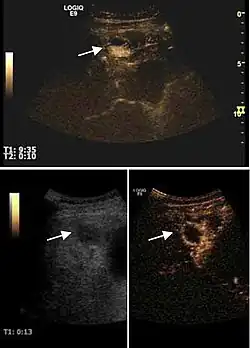

Fig. 13. Assessment of therapeutic efficacy on ultrasound (2D, CFM, CEUS). US exam shows vascular Doppler signal at CFM (left) and CEUS examination reveals incomplete therapy (right).

Fig. 14. Small HCC is seen at top (nodule in nodule). Efficient chemoembolization of the nodule (bottom). CEUS examination shows no circulatory signal within the nodule.

Currently, local response to treatment is focused on tumor necrosis diagnosed by contrast dynamic imaging techniques and recognized by the presence of intratumoral non-enhanced areas. Local response to treatment is defined as: a. complete response, defined as complete disappearance of all known lesions (absence of tumor enhanced areas, reflecting total tumor necrosis) and absence of other new lesions determined by two observations not less than 4 weeks apart; b. partial response, defined as more than 50% reduction in total tumor enhancement in all measurable lesions, determined by two observations not less than 4 weeks apart c. stable disease (is not described by a, b, or d) d. progressive disease, defined as 25% increase in size of one or more measurable lesions or the appearance of new lesions.

2D ultrasound, Doppler ultrasound and especially CEUS can play an important role in pretherapeutic staging, particularly when sectional imaging investigations (CT, MRI) provide uncertain results or are contraindicated. During the interventional procedure, ultrasound allows guidance of the needle into the tumor. CEUS allows guidance in areas of viable tissue and avoids intratumoral necrotic areas. CEUS also allows assessment of therapeutic effect immediately post-procedure (with the possibility of reintervention in case of partial response) . To accurately assess the effectiveness of treatment it is mandatory to compare the tumor diameter before therapy with the ablation area. The volume of damaged tissue must be higher than the initial tumor volume. CEUS appearance is that of central nonenhanced area showing a peripheral homogeneous hyperenhanced rim due to post-procedure inflammation. 24 hours after the procedure the inflammatory peripheral rim is thinning and the necrotic area appears larger than at the previous examination. Thus, a possible residual tumor may appear more evident. Residual tumor has poorly defined edges, irregular shape, and the tumor diameter is unchanged. Residual tumor tissue is evidenced at the periphery of the tumor as an eccentric area behaving as the original tumor at CEUS examination, with arterial hyperenhancement and portal and late wash-out. Ultrasound examination 24 hours after the procedure, including CEUS, can show apart from the character of the lesion any potential post-intervention complications (e.g. active bleeding).

Local recurrence is defined as recurrence of a hyperenhanced area at tumor periphery in the arterial phase, with portal and late wash-out. Sometimes, especially for HCC treated by alcoholization (PEI) hyperenhanced septa or vessels can be shown inside the lesion.